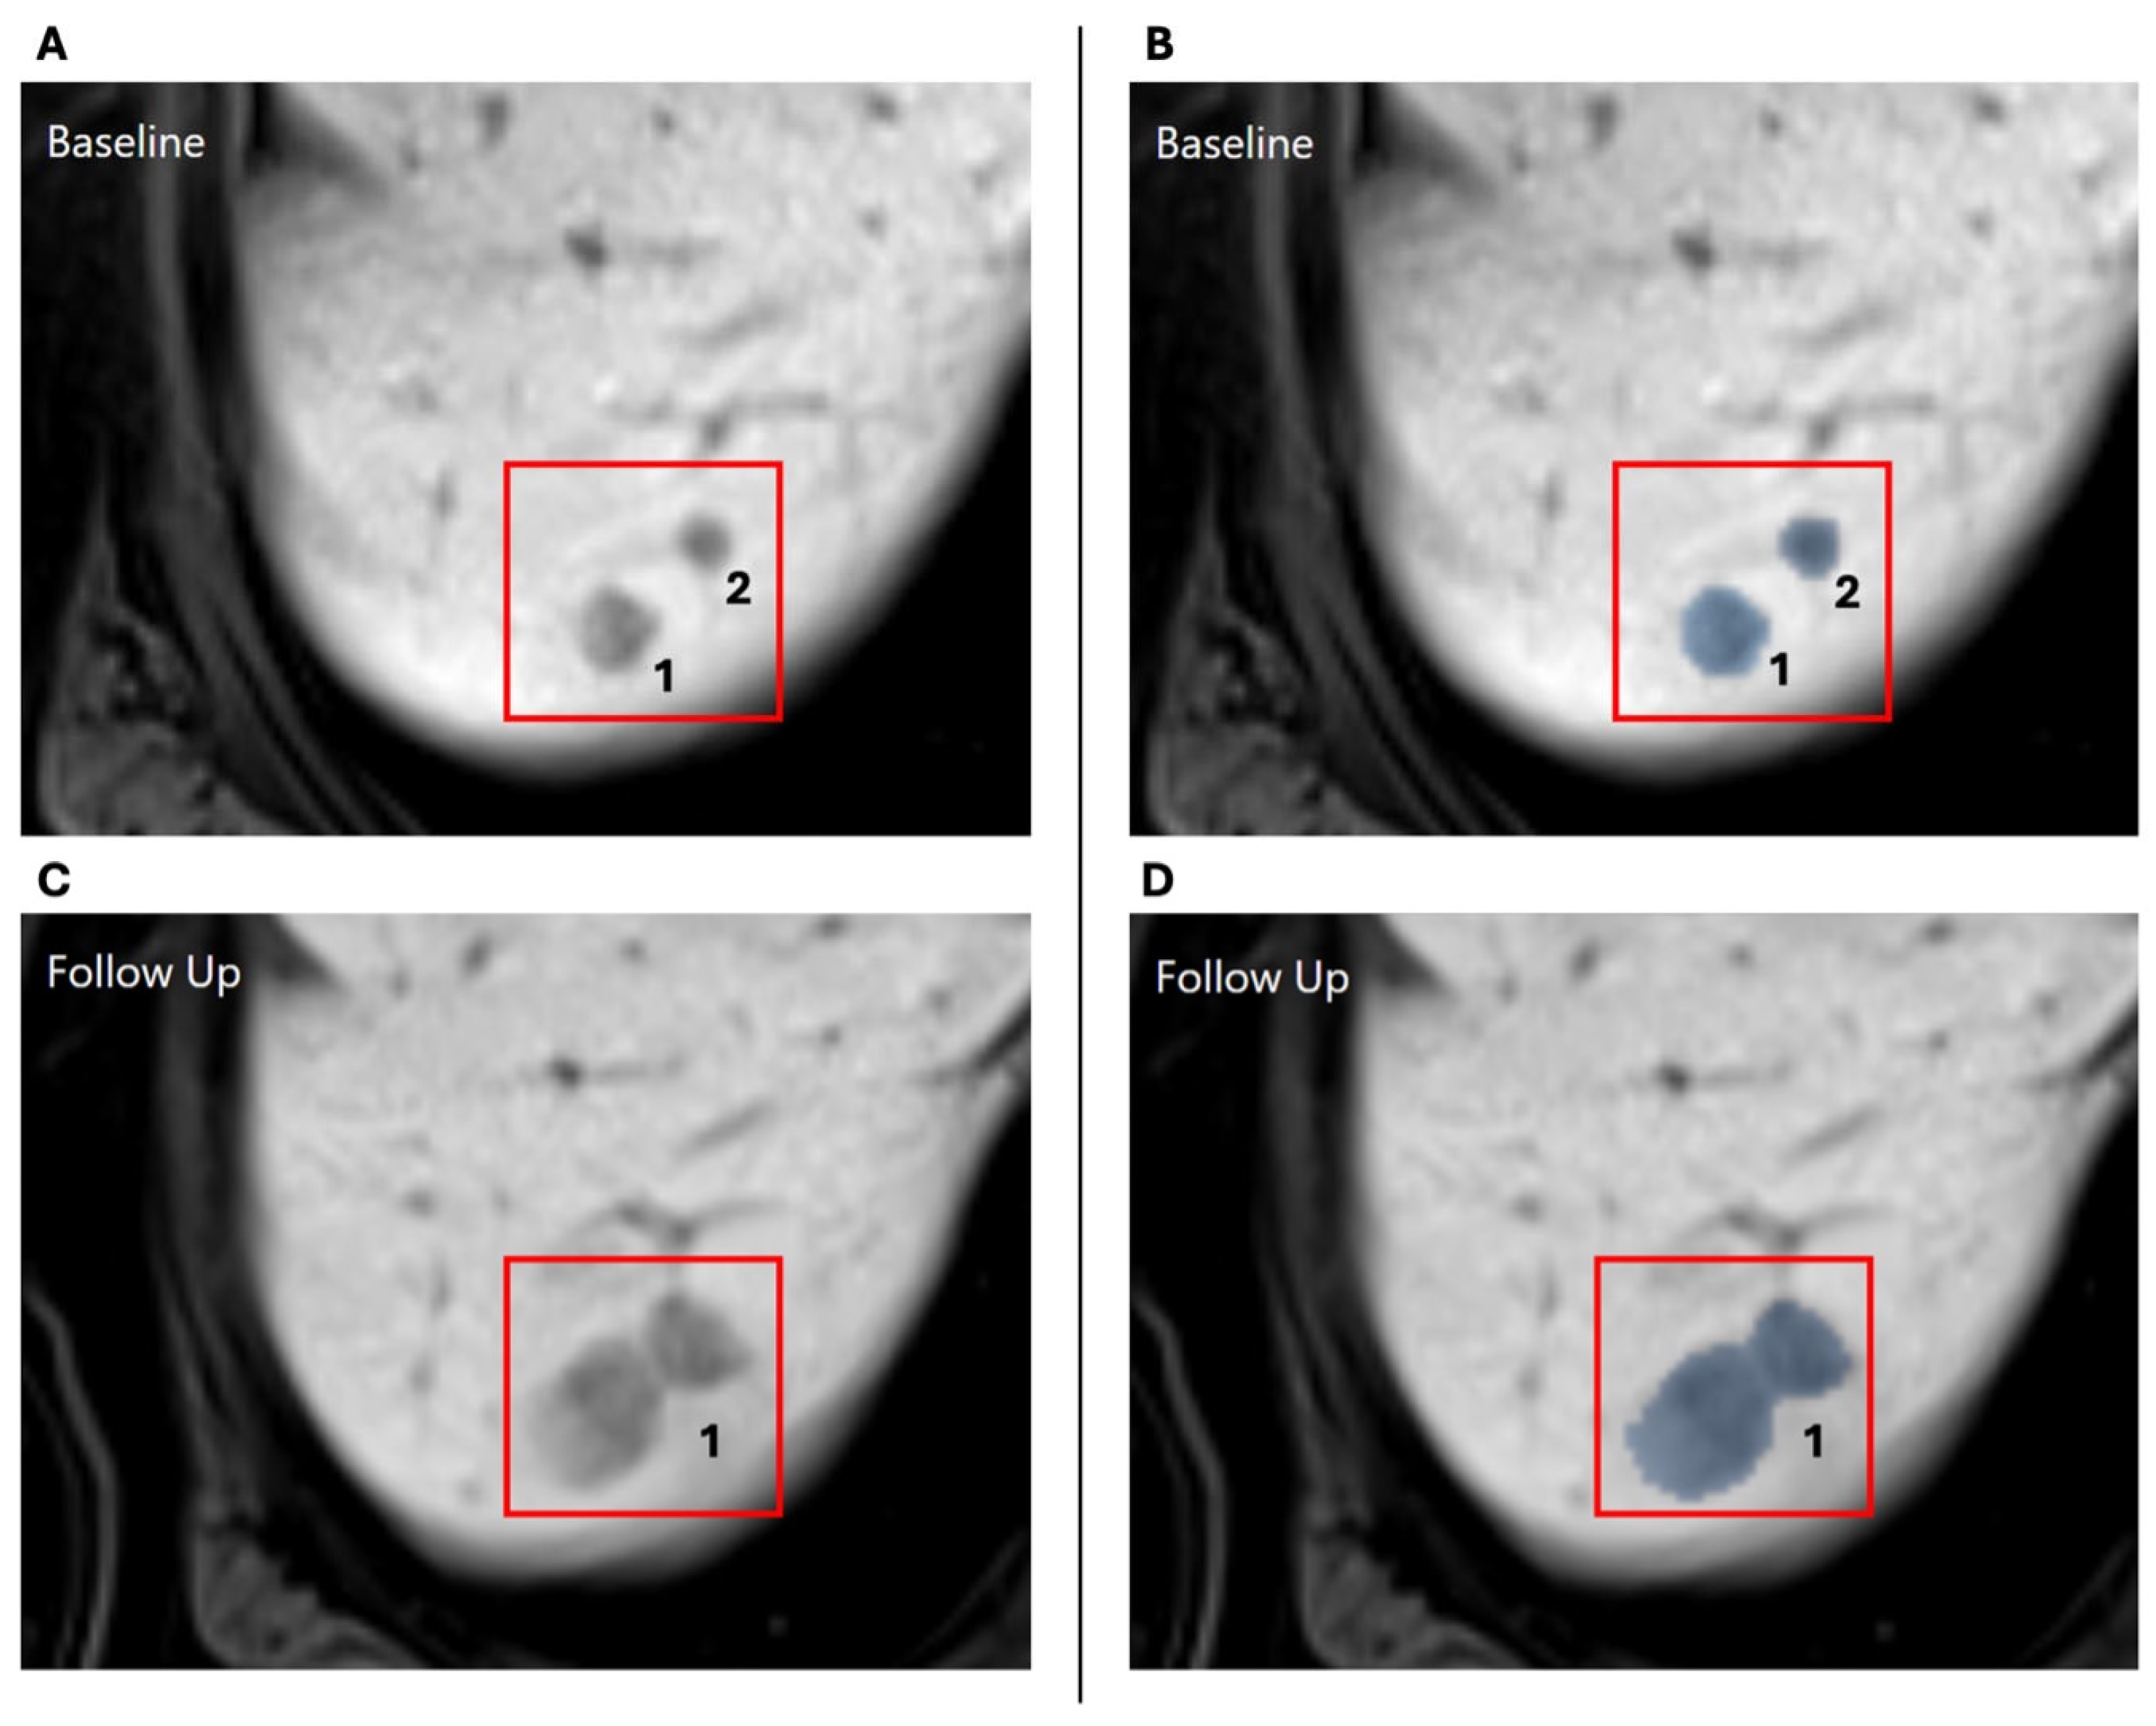

2.2. Automatic Lesion Detection and 3D Tracking

| Progressive | The diameter increased by at least 20% |

| Stable | The diameter change is between 20% increase and 30% decrease |

| Regressive | The diameter decreased by at least 30% |

| New | The lesion only appears in the follow-up MRI |

| Merged | The lesion grew together with another lesion |

| Too small to measure | The lesion has a diameter smaller than 5 mm at both timepoints |